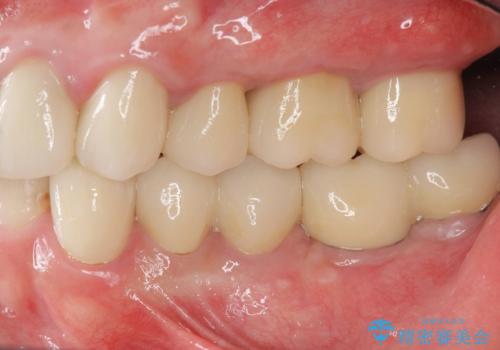

虫歯の再発による抜歯後のインプラント治療

抜歯後、骨の再生を待ったことで、清掃性の高い位置に埋入を行い機能的・審美的なインプラント治療を行うことができました。